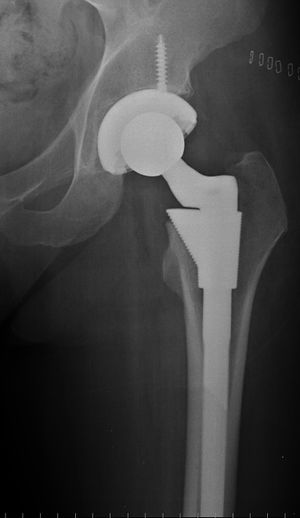

مفصل ورك صناعي مخلوع